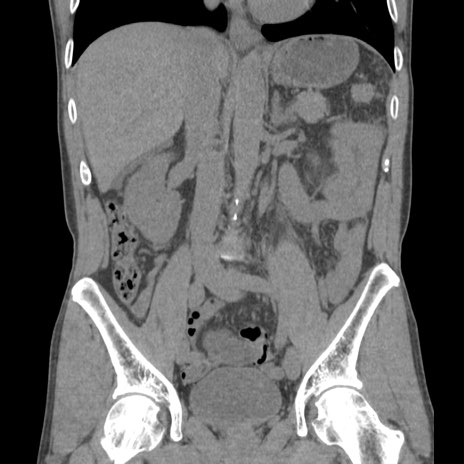

症例56 CT(冠状断像)

脂肪ウインドウ